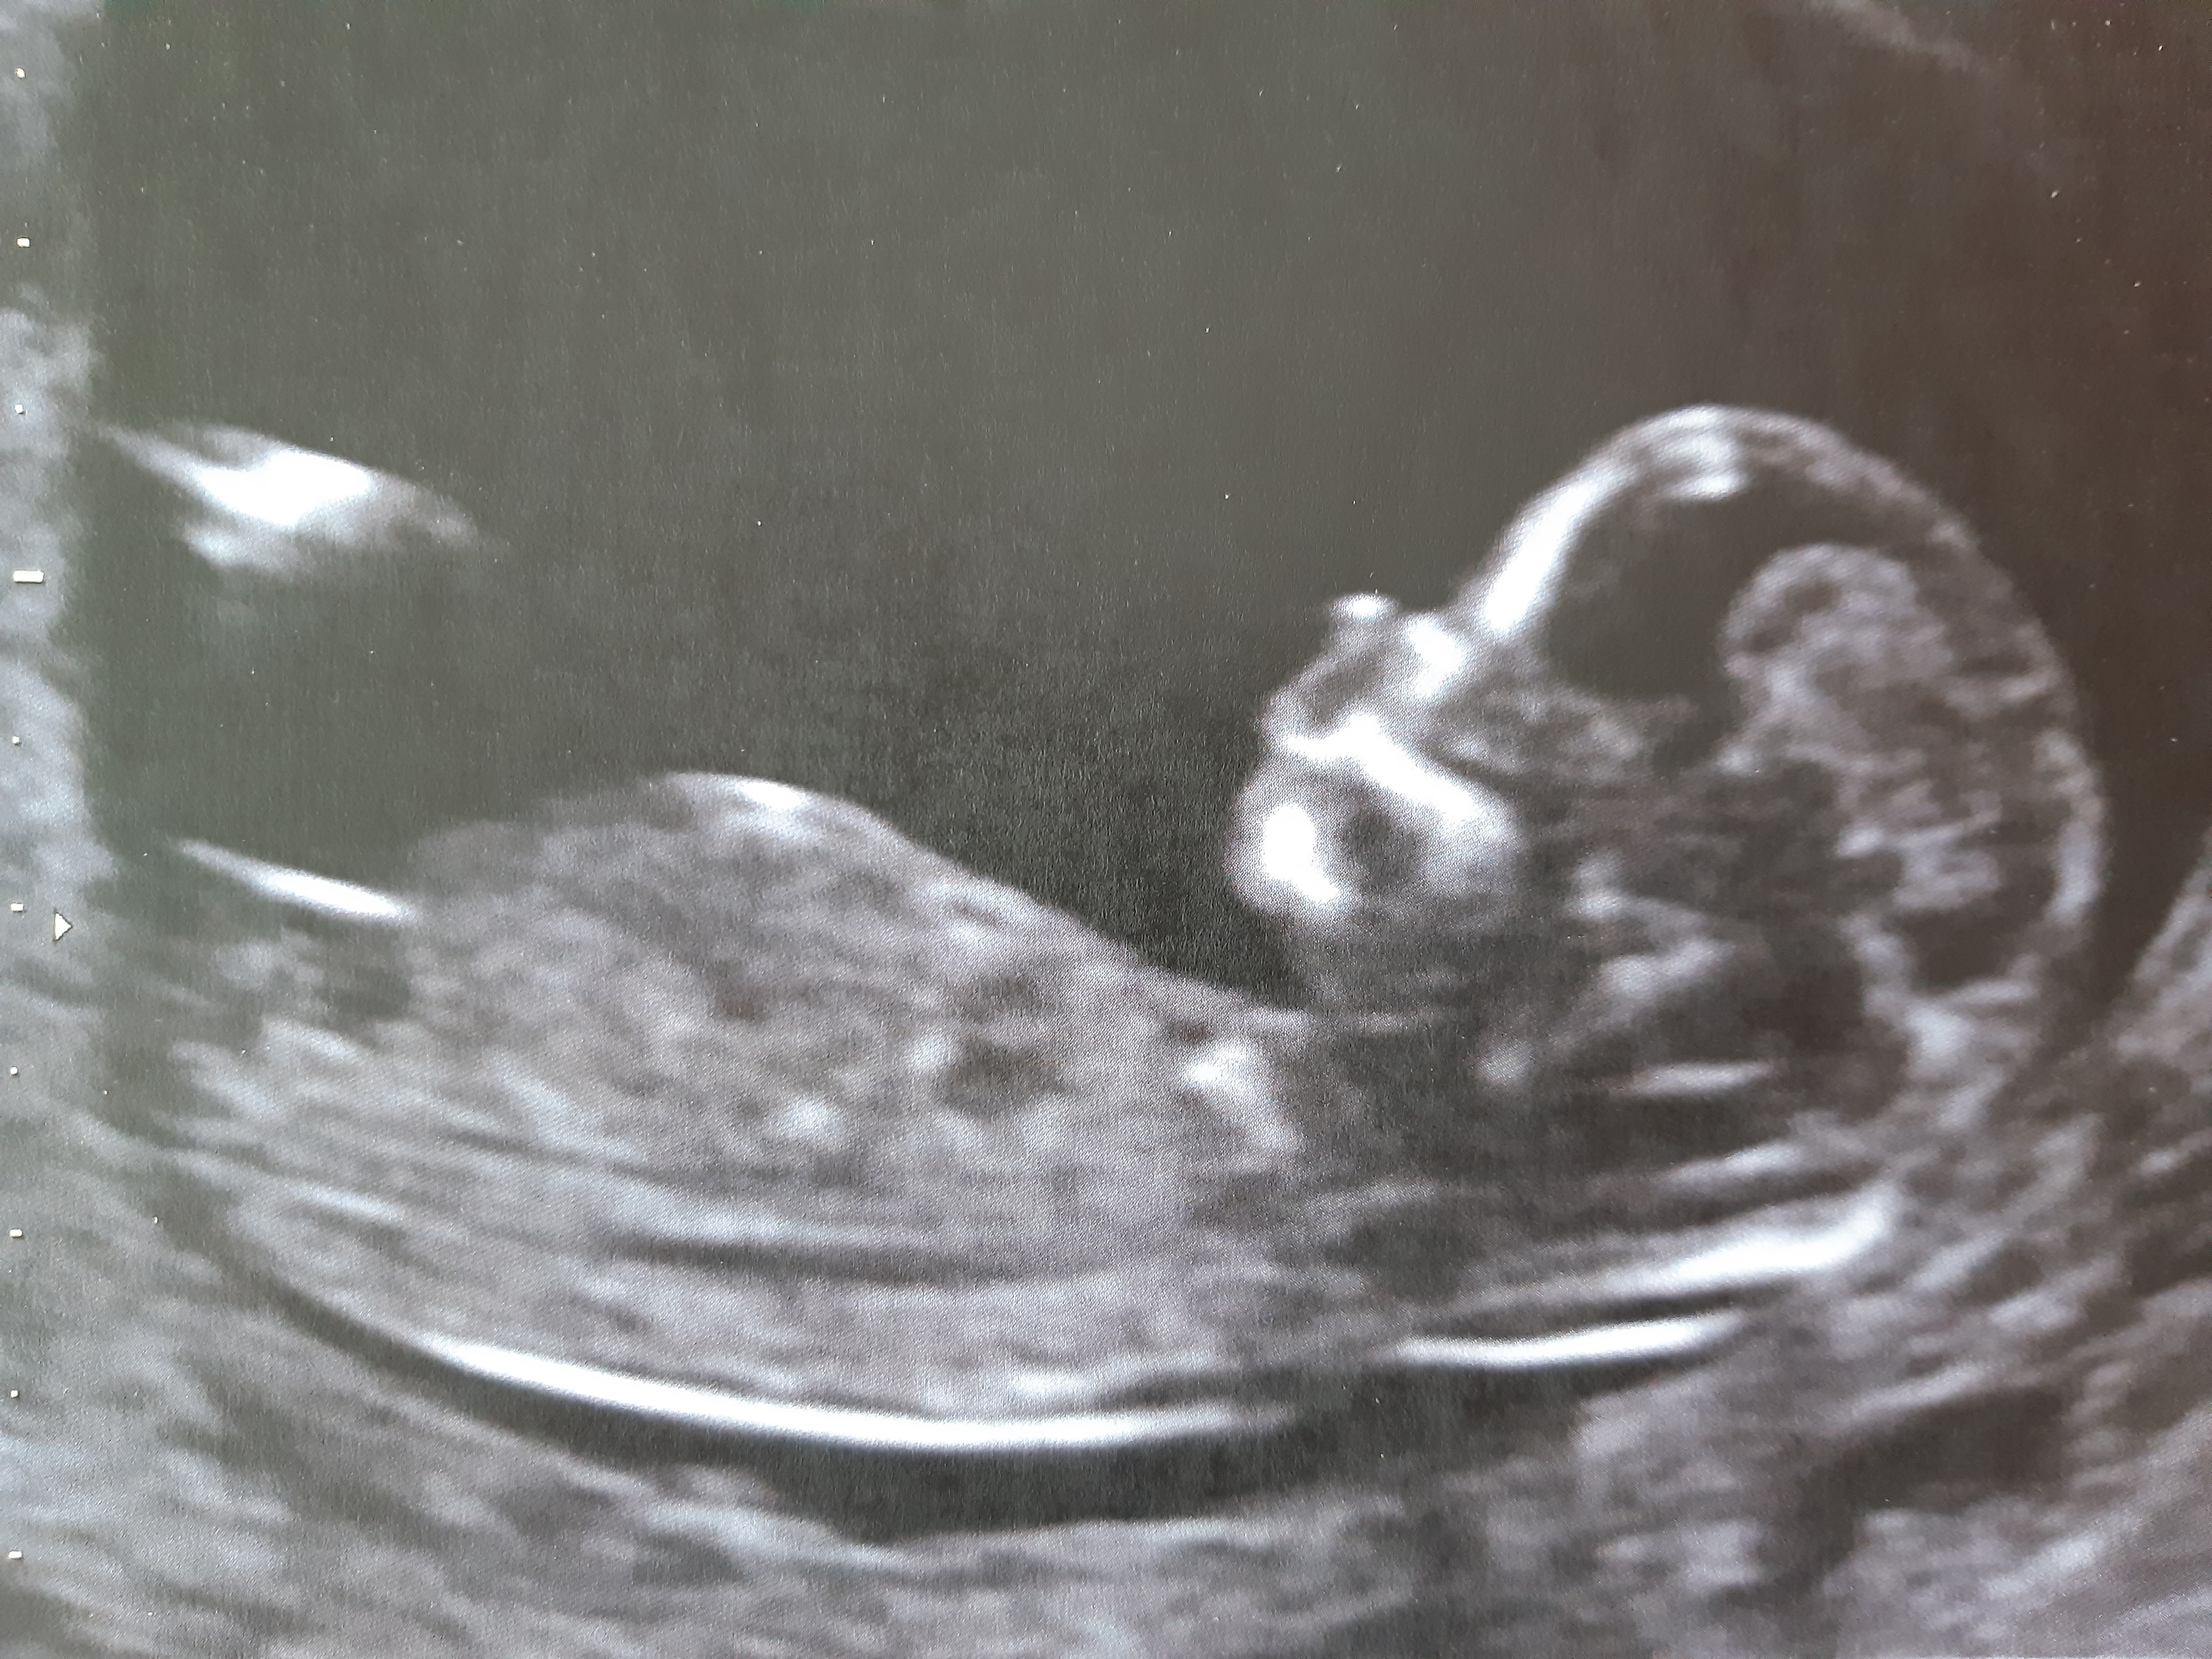

- l’échographie du 1er trimestre vers 12 SA (semaines d'aménorrhée), au cours de laquelle la datation sera définitivement réalisée, ainsi que la mesure de la clarté nucale de votre bébé dans le cadre du dépistage de la trisomie 21 (non obligatoire mais qui vous sera systématiquement proposé ce jour-là).

- l’échographie du 2e trimestre vers 22 SA, consacrée à l’étude morphologique rigoureuse de votre bébé, son anatomie, ses organes, l’estimation de son poids.

- l’échographie du 3e trimestre vers 32 SA, permettant entre autre d’évaluer sa croissance et de vérifier sa position pour l’accouchement.

Il est possible que l’on vous propose aussi une échographie plus précoce vers 8-9 SA, ou toute autre échographie intermédiaire nécessaire à la surveillance optimale du bon déroulement de votre grossesse.